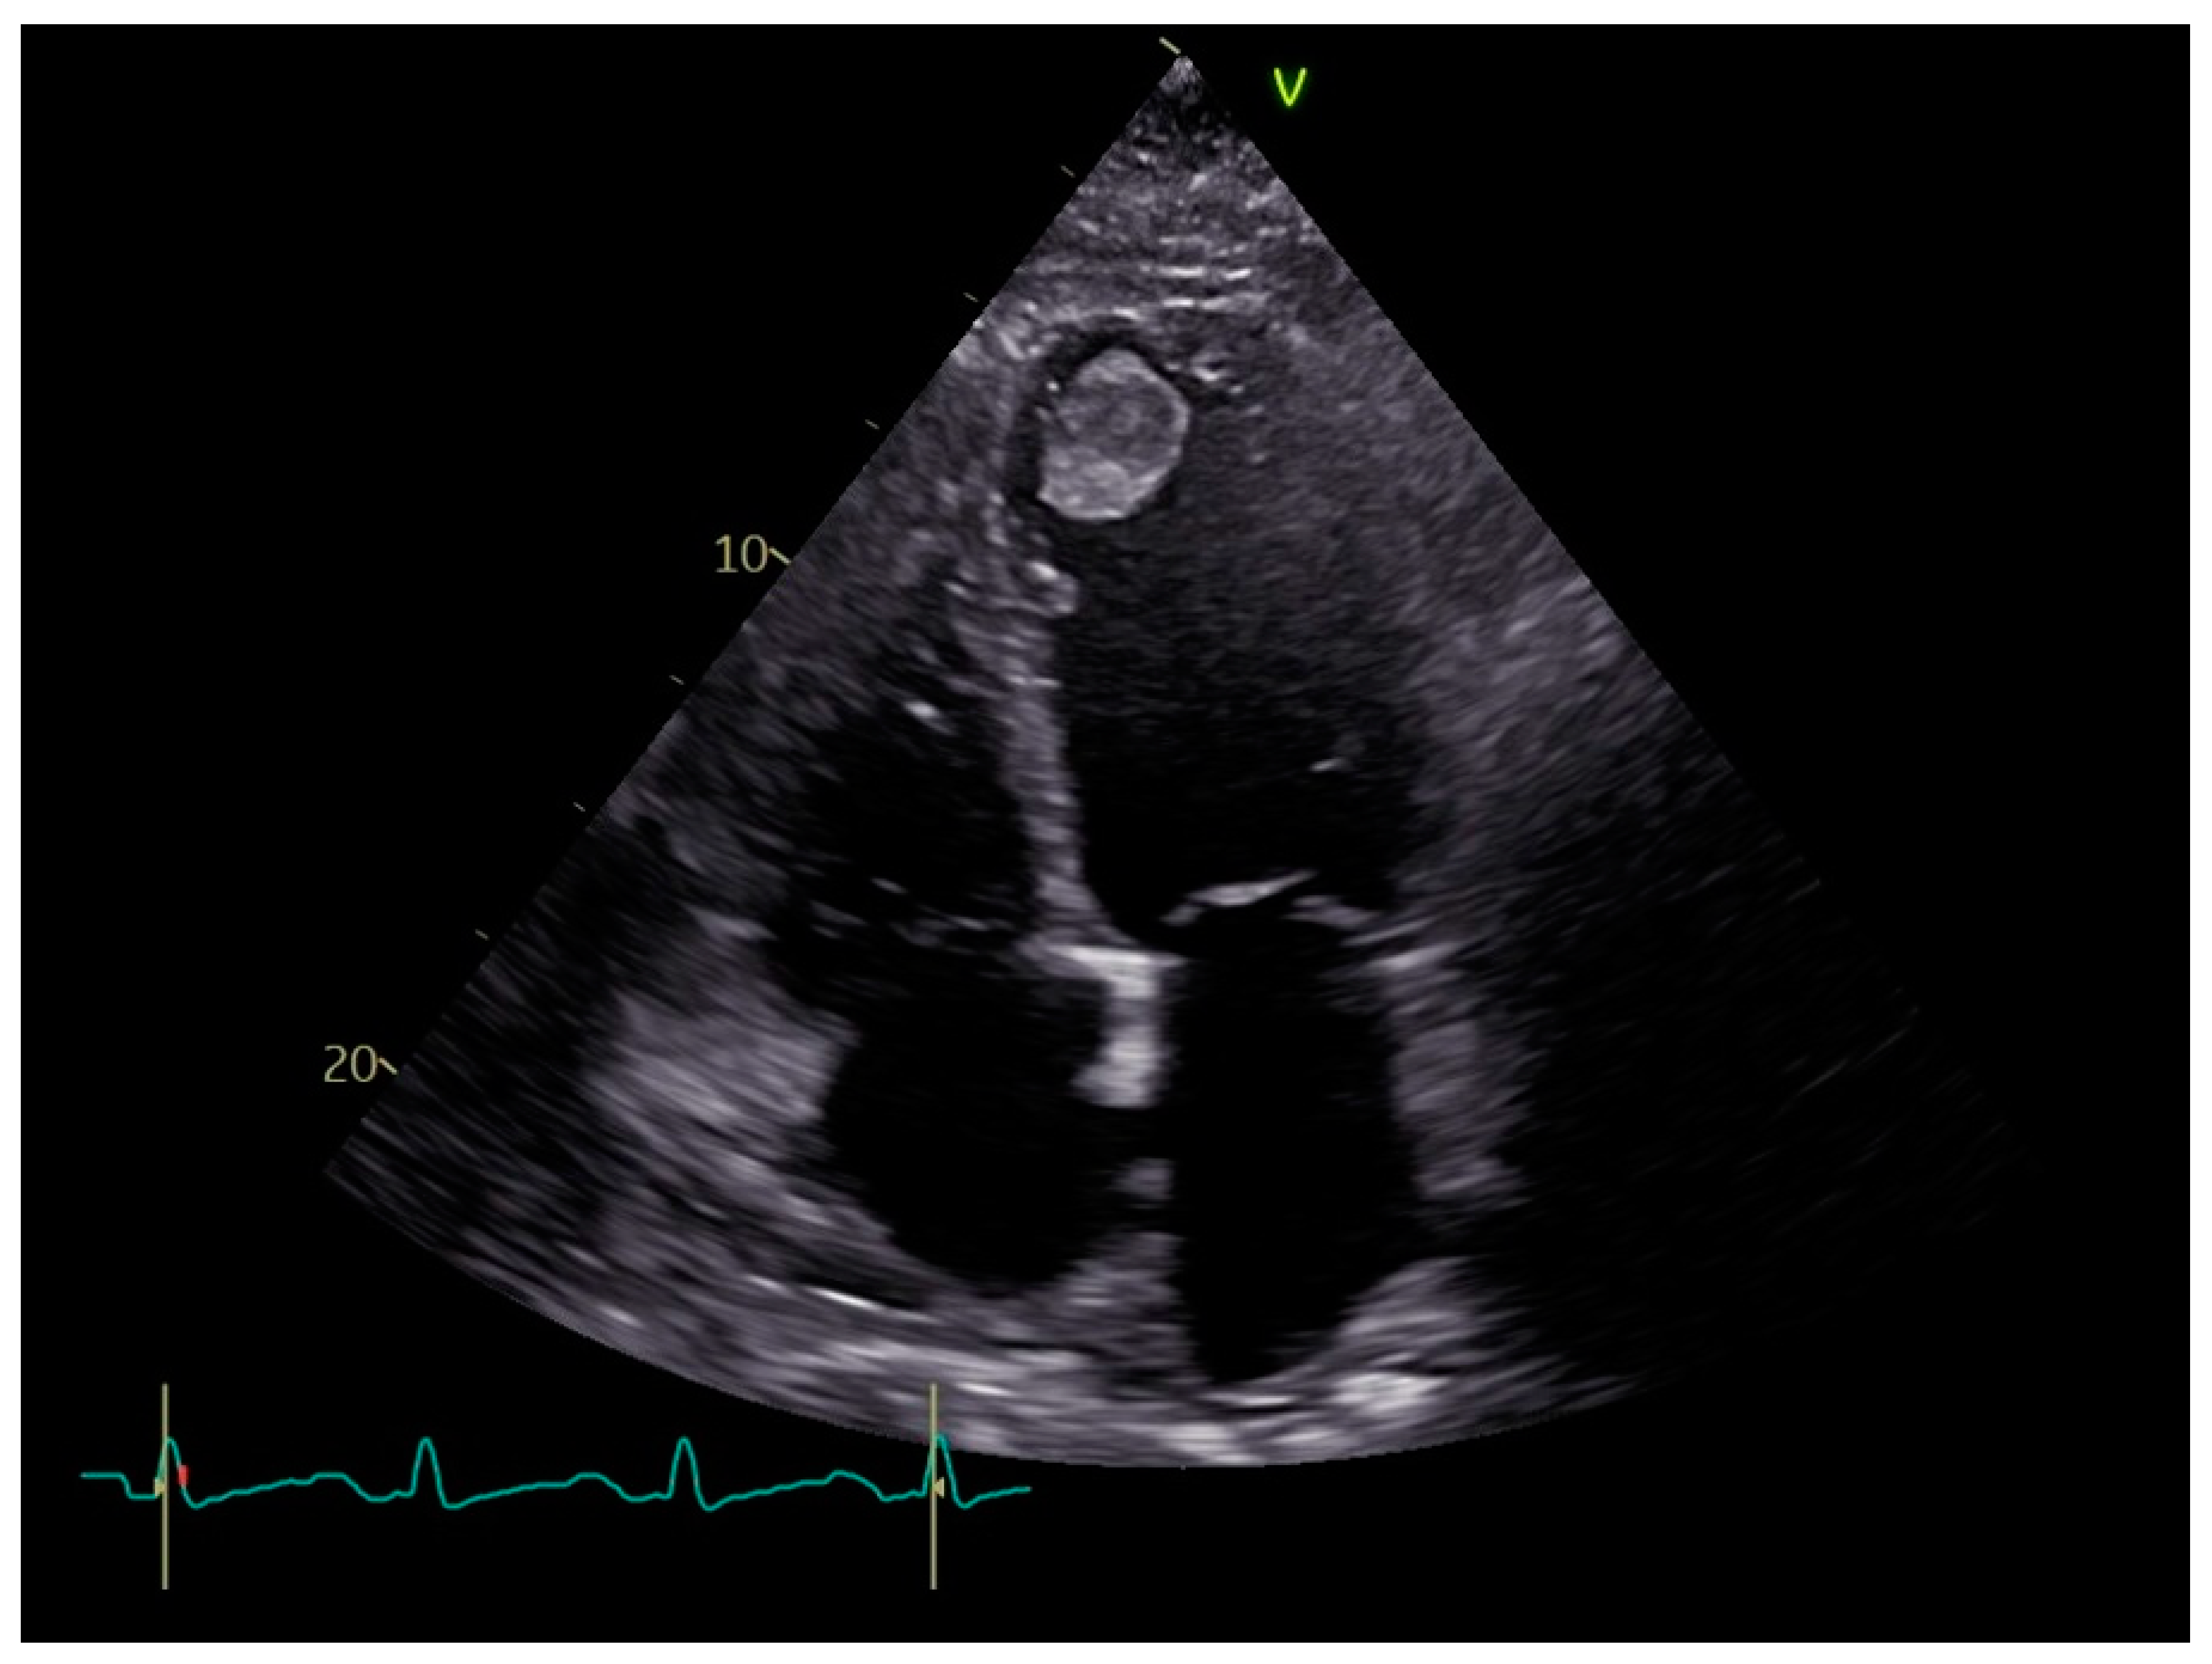

4. Diagnosis

- Saric, M.; Armour, A.C.; Arnaout, M.S.; Chaudhry, F.A.; Grimm, R.A.; Kronzon, I.; Landeck, B.F.; Maganti, K.; Michelena, H.I.; Tolstrup, K. Guidelines for the Use of Echocardiography in the Evaluation of a Cardiac Source of Embolism. J. Am. Soc. Echocardiogr. 2016, 29, 1–42. [Google Scholar] [CrossRef]

- Srichai, M.B.; Junor, C.; Rodriguez, L.L.; Stillman, A.E.; Grimm, R.A.; Lieber, M.L.; Weaver, J.A.; Smedira, N.G.; White, R.D. Clinical, imaging, and pathological characteristics of left ventricular thrombus: A comparison of contrast-enhanced magnetic resonance imaging, transthoracic echocardiography, and transesophageal echocardiography with surgical or pathological validation. Am. Heart J. 2006, 152, 75–84. [Google Scholar] [CrossRef]

- Phuah, Y.; Tan, Y.X.; Zaghloul, S.; Sim, S.; Wong, J.; Usmani, S.; Snell, L.; Thavabalan, K.; García-Pérez, C.L.; Kumar, N.S.; et al. A systematic review and meta-analysis of transthoracic echocardiogram vs. cardiac magnetic resonance imaging for the detection of left ventricular thrombus. Eur. Heart J.—Imaging Methods Pract. 2023, 1, qyad041. [Google Scholar] [CrossRef] [PubMed]